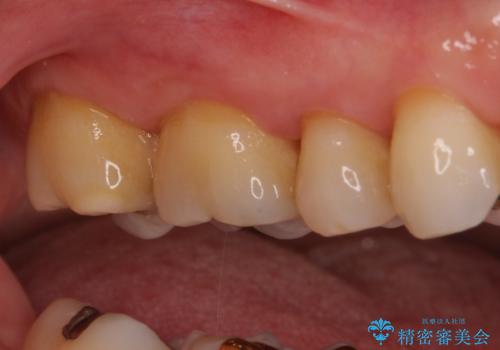

ゴールドインレーは銀歯のインレーやセラミックインレーと比べ、「技工操作の精度が高く、適合が著しく良い」というメリットがあります。特に上の奥歯は歯科医師の操作が行いにくいため、「適合の良さ」は再治療のリスクを防ぐ上でとても重要な要素となります。

上の奥歯は金属色が見えることもないため、審美的な問題は全くありません。

咬み心地はとても良好で、全く違和感がなく、患者様には大変満足していただきました。